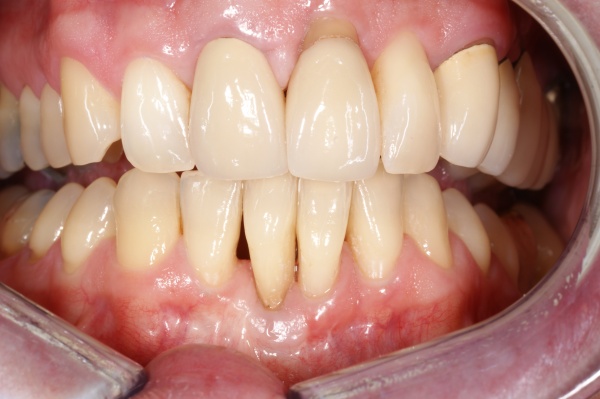

Mit der Transplantation eines freien Schleimhauttransplantats im Januar 2001 konnte die aktive parodontologische Therapie abgeschlossen werden, der Patient wurde zur Unterstützenden Parodontitistherapie in das Recallsystem der FU VIIa aufgenommen. Der Patient stellte sich dabei halbjährlich zur Durchführung von professionellen Zahnreinigungen vor, die durch die bereits beschriebenen Elemente der Erhaltungstherapie ergänzt wurden. Ein wichtiges Element der Erhaltungstherapie ist die regelmäßige parodontale Diagnostik mit der Erstellung eines Parodontalstatus, um gegebenenfalls Rezidive frühzeitig erkennen und behandeln zu können. Im Jahre 2006 kam es an einzelnen Zähnen zu Rezidiven, es konnten Sondiertiefen von bis zu 7mm sondiert werden. Es wurde daher ein Scaling/Rootplaning der rezidivierenden Taschen durchgeführt, an einzelnen Zähnen erfolgten im Jahre 2008 zudem weiterführende parodontalchirurgische Maßnahmen im Sinne von Lappenoperationen (s. Abb. 16). Im Rahmen der unterstützenden Parodontitistherapie erfolgte neben den schon erwähnten halbjährlichen professionellen Zahnreinigungen im November 2012 eine erneute subgingivale Instrumentierung an 21, 24, 28, 41, 46. Die letzte Vorstellung des Patienten erfolgte im April 2015 (s. Abb. 17, 18, 19). Dabei stellte sich die marginale Gingiva entzündungsfrei dar, die approximalen Sondiertiefen betrugen durchschnittlich zwei bis drei Millimeter, geringgradig erhöhte Sondiertiefen verbleiben an 21, 28, 36, 47. Die häusliche Mundhygiene des Patienten stellte sich wie schon über den gesamten Beobachtungszeitraum mit einem API von 30 % als gut dar. Die periimplantären Gewebe zeigten sich bei der Vorstellung im April 2015 unauffällig.